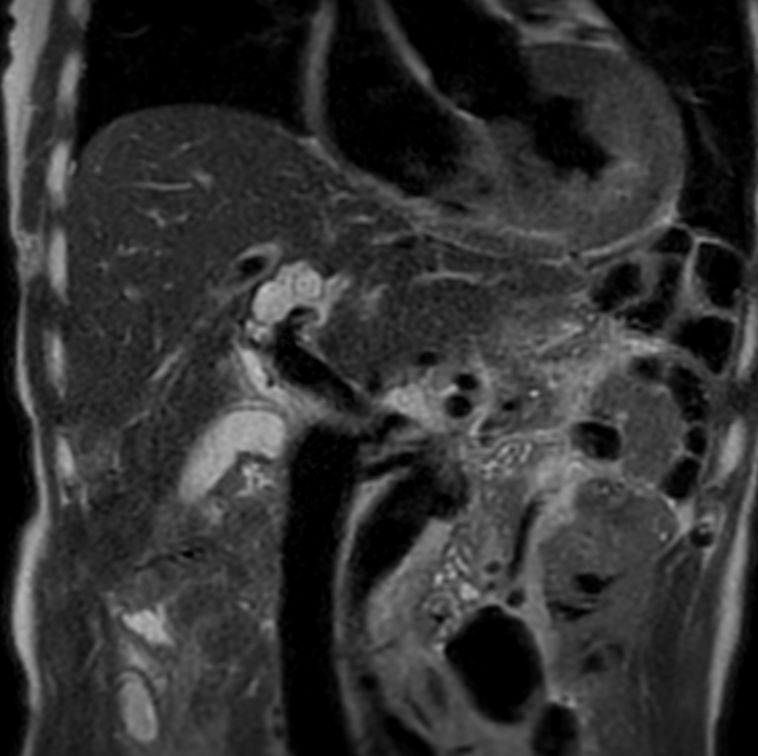

3D MRCP

3D MRCP - Compressed SENSE